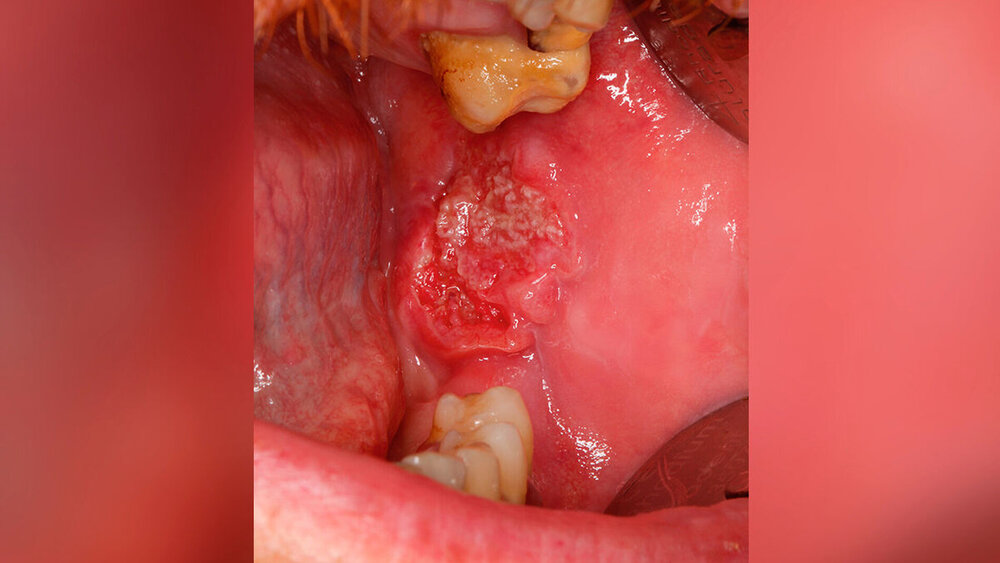

Beim Erstkontakt präsentierte sich der Patient in gutem Allgemein- und Ernährungszustand. Anamnestisch bestanden keine bekannten Vorerkrankungen oder Auffälligkeiten in der Familienanamnese. Die klinische Untersuchung der Mundhöhle zeigte einen circa 4 cm x 3 cm großen, exophytisch wachsenden Befund im Bereich des linken Planum buccale (Abbildung 1). Eine Probeentnahme in Lokalanästhesie bestätigte die Verdachtsdiagnose eines p-16 negativen Plattenepithelkarzinoms.